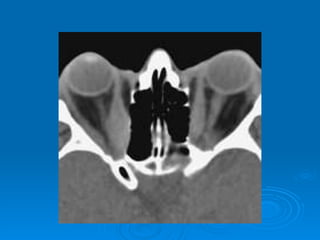

 THYROID EYE DISEASE

Thyroid Eye Disease

 may occur in the absence of biochemical

evidence of thyroid dysfx

 autoimmune reaction (IgG Abs) causing:

   inflammation of EOMs: pleiomorphic cellular

infiltration associated with increased secretion

of GAGs and osmotic imbibition of water

• muscles can become up to 8 times their original

size!!

 no relation to severity of thyroid dysfx!

 main findings: (not all are always present!)

   soft tissue involvement

   lid retraction

   proptosis

   optic neuropathy

   restrictive myopathy

 vision loss from:

   exposure keratopathy

• due to severe proptosis resulting in incomplete lid

closure → chronically exposed cornea → corneal

ulceration & exposure keratopathy

• affects 5% of pts

• compression of ON or its blood supply by

congested (enlarged) EOMs

• can lead to severe, permanent visual impairment

• rx with steroids, surgery if needed